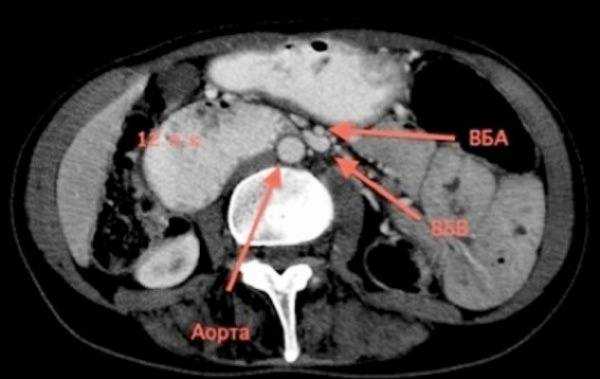

Выявить стеноз висцеральных артерий можно при помощи ультразвукового дуплексного сканирования сосудов брюшной полости, при прямой ангиографии и мультиспиральной компьютерной томографии-ангиографии.

1. Стеноз чревного ствола (снабжает кровью печень, селезенку, желудок, поджелудочную железу)

Это состояние, при котором просвет чревного ствола сужается, может быть приобретенным - развивается при поражении сосуда атеросклерозом, либо врожденным - при сдавлении извне дугообразной связкой диафрагмы (значительно реже — при воспалительных заболеваниях, аневризмах аорты, врожденных аномалиях развития, сдавлении новообразованиями брюшной полости). Первая причина часто сочетается с поражением других артерий (коронарных — внутрисердечные артерии, сонных, артерий нижних конечностей), вторая причина — врожденное состояние, проявления которого развиваются в молодом возрасте. Основными органами, испытывающими недостаток кровоснабжения, являются желудок, печень и поджелудочная железа, однако за счет "синдрома обкрадывания" страдает и кишечник. Значимым сужением просвета артерии в настоящее время считается более 50% от первоначального диаметра. Симптомы заболевания - боли в животе, вздутие, нарушения стула в виде чередующихся поносов и запоров, тошнота, потеря веса объединяются в единый синдром — синдром "хронической абдоминальной ишемии" (хроническая ишемическая болезнь органов пищеварения, абдоминальная ишемическая болезнь).

Установить причину сужения сосуда можно при помощи:

- дуплексного сканирования сосудов брюшной полости,

- выполнения ангиографии либо мультиспиральной компьютерной томографии — ангиографии (МСКТ-ангиография).

- Эндоваскулярная балонная ангиопластика со стентированием чревного ствола. Это вмешательство выполняется через прокол в бедренной, реже - в других артериях. При помощи специальных тонких инструментов суженный участок чревного ствола расширяется изнутри до восстановления нормального диаметра просвета и устанавливается стент — тонкий «каркас» из инертных сплавов, в дальнейшем препятствующий повторному сужению артерии. Применяется чаще всего при поражении чревного ствола атеросклерозом.